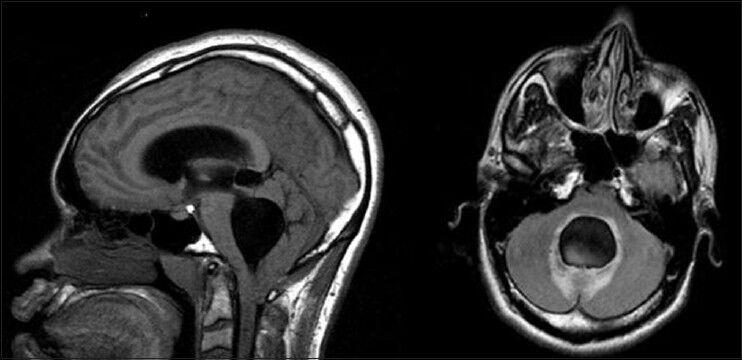

Chiari malformation type 1 (CM1) is a common congenital anomaly of the craniocervical junction. CM1 is reported to run a usually benign course and patients typically experience no symptoms or chronic, slowly progressive symptoms. However, recent reports indicate that a subset of patients with CM1 may present with acute deterioration and sudden unexpected death (SUD). We report a case of SUD during sleep in a young man with CM1, which we believe was related to the administration of common and therapeutic doses of narcotic analgesics for the management of pain. We will clarify the pathophysiology of acute deterioration and SUD in CM1 and the possibility that the adverse effects of opiate analgesics likely were the leading cause of death in our patient.

In this review, we present a 29-year-old male with worsening headache secondary to previously diagnosed CM1. The patient died suddenly and unexpectedly after administration of common and therapeutic doses of narcotic analgesics for the management of pain.